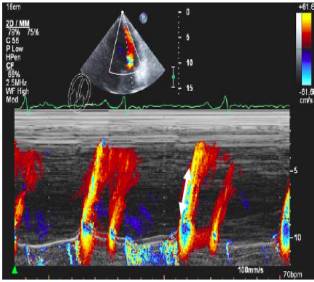

14、彩色M型血流传播速度—VP

VP=39cm/s(正常值>50cm/s)